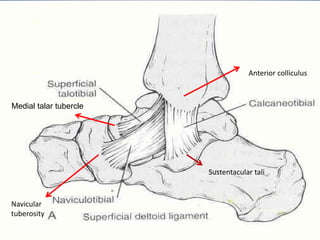

2. MEDIAL LIGAMENT COMPLEX

SUPERFICIAL(little contribution to stability)

>Tibionavicular ligament

>Tibiocalcaneal ligament

>Superficial tibiotalar ligament

DEEP( primary medial stabilizer)

>Intraarticular

>Deep tibiotalar lig.

-stabilize the joint during eversion and

prevent talar subluxation

-20-50% stronger than lateral ligaments

Medial talar tubercle

Navicular

tuberosity

Anterior colliculus

Sustentacular tali